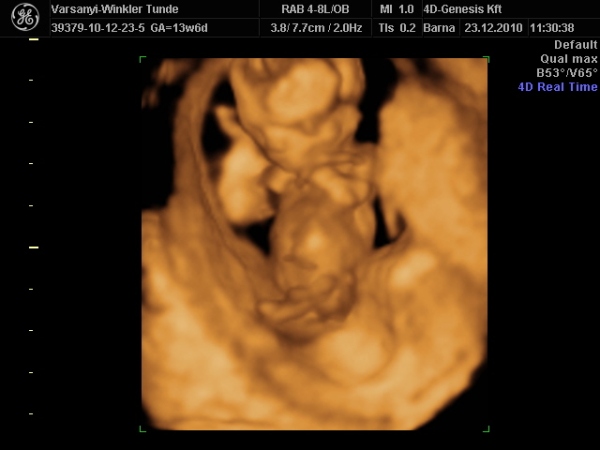

Bár tegnap a dokor bácsi azt mondta, hogy azért lassan vissza kellene vennem a lendületből, mert nem lesz jó vége. Manócska jól van, de tegnap nem tudtuk megnézni. Hasi uh-val próbálkozott, de pont úgy fordult, hogy csak a nagy kobakját láttuk

Gondolta, ha arra van a feje, akkor lentről lehet látni valamit a neméből.

Be is terpesztett rendesen, mint egy kis utcalány

Természetesen lánynak is látszott, bár azt mondta, hogy még ne éljük bele magunkat. A férjem le is tört egy kicsit, de nem vallotta volna be.Holnap reggel megyek AFP-re.